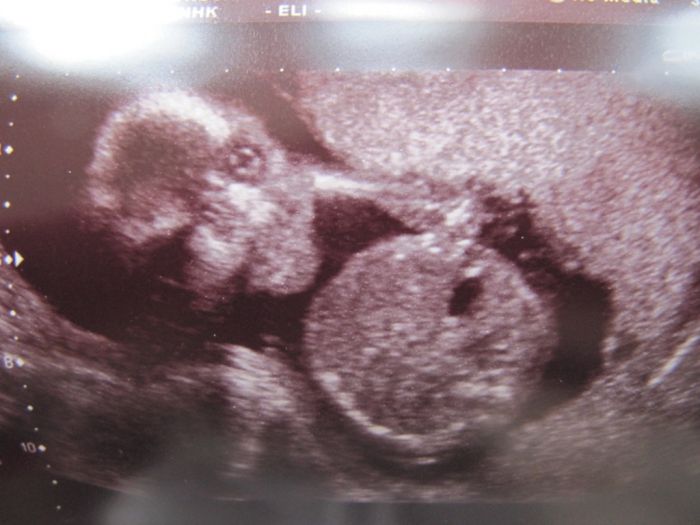

Tak se hlásím po dnešní genetice, zdá se být všechno v naprostém pořádku, tak jsem šťastná jak blecha, teď ještě v tom 20tt., ale věřím, že když dopadlo tohle dobře, tak i ten velký bude v pořádku. Je to definitivní kluk, pan profesor mi udělal i 3 fotky, jako dáreček (bez placení, na pohlaví jsem se neptala-sám se nabídnul, zda to chci vědět). Tak je připojuju, na jedné je z profilu s otevřenou pusinkou, na jedné zepředu-pěkně viditelná čočka v jednom oku a na poslední výbavička našeho frajera.

Marse: na té první to vypadá, jak by se tvůj chlapeček zrovna něčemu chechtal